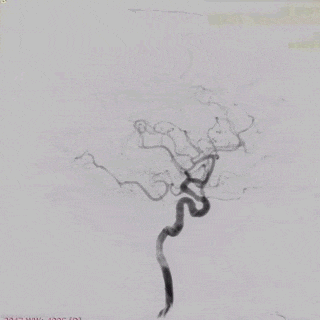

术后即刻造影。

术后重建。